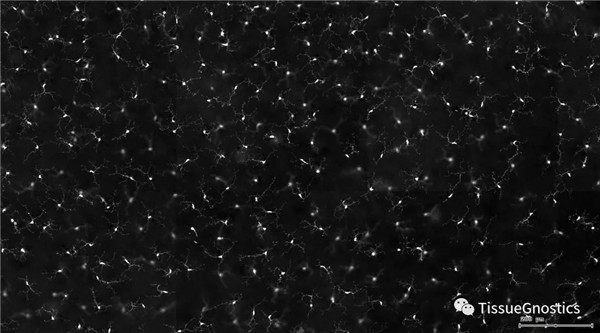

一般而言,眼底圖像通常都是通過激光掃描成像進行采集,但是由于眼底可觀測的視野往往是很有限的,一個患者的眼底信息需要多張掃描圖像才能完全顯示出來。這種局限性大大不利于病情進行全面的、細致的診斷。Tissue Cytometry全景組織流式定量分析技術(shù)進行全景圖像獲取,在單細胞、組織結(jié)構(gòu)、細胞空間信息等多個層面進行定位、定性、定量分析。從而更好的對病變區(qū)域進行有針對性的跟蹤觀察和全面分析。

視網(wǎng)膜熒光樣本中小膠質(zhì)細胞胞體、神經(jīng)纖維識別、血管識別、血管斑點識別、神經(jīng)元與血管的距離分析。

1. 利用TissueFAXS系統(tǒng)進行玻片熒光的全景掃描。

單通道灰階圖(↑:FITC,↓:Texa Red)